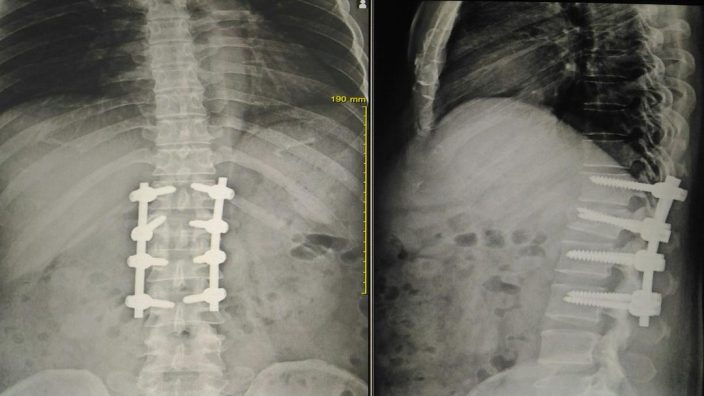

Czym jest technika UBE?

Unilateral Biportal Endoscopy (UBE) to małoinwazyjna metoda leczenia schorzeń kręgosłupa. Polega na wprowadzeniu dwóch kanałów endoskopowych (kamera i narzędzia chirurgiczne) przez małe nacięcia w skórze. Dzięki temu zabieg jest mniej inwazyjny niż tradycyjna operacja kręgosłupa, a pacjenci szybciej wracają do zdrowia.